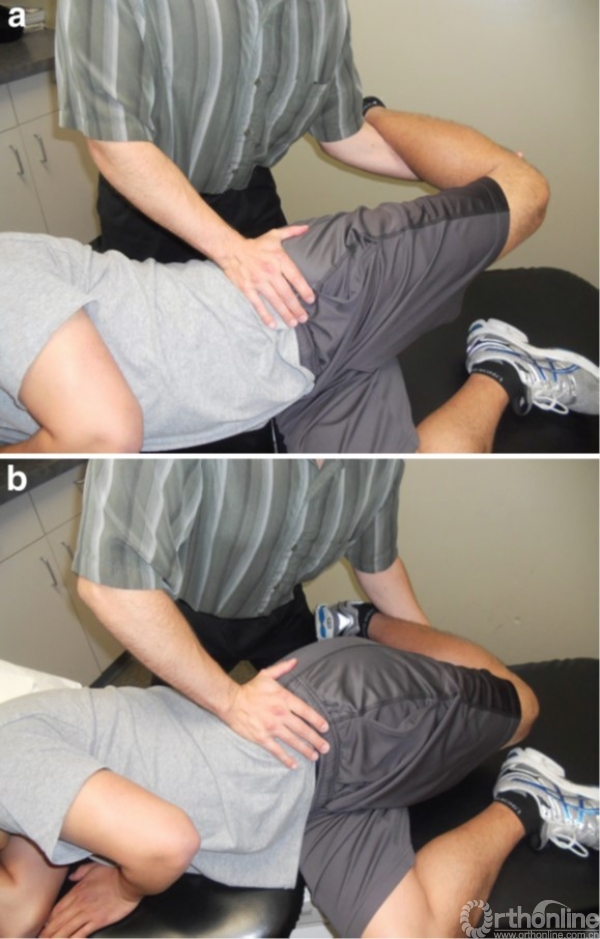

(1)骨盆按压检查

骨盆按压检查

骨盆按压检查是2007年由Nouraei等人首次描述,其诊断MP的敏感性为95%,特异性为93.3%。检查方法:患者处于侧卧姿势,症状腿在上。检查者施加一个向下的压力在骨盆上,保持压力45秒。如果病人诉症状缓解则认为是阳性。

(2)神经张力检查

神经张力检查

由Butler提出,检查方法:患者侧卧症状腿在上,下腿屈膝。检查者用手固定骨盆,另一只手抓住症状腿的膝关节处,然后使膝关节弯曲、臀部内收以使LFCN张力升高。患者如果神经症状再现并且臀部软组织感到变紧则为阳性。